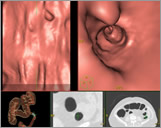

CT kolonografija ili virtualna kolonoskopija je procedura koja koristi viseslojni CT za pregled debelog crijeva na prisustvo karcinoma ili prekanceroznih polipa. Njome se mogu otkriti tumori, polipi, krvarenje, upalne bolesti crijeva te divertikuloza.

Iza 40-te godine života svi, dakle i pacijenti koji nemaju nikakvih tegoba bi trebali uraditi kolonoskopiju svakih 10g ukoliko je nalaz uredan te bez obzira na godine svi koji imaju određenih probavnih problema (krv u stolici, nadimanje, zatvor, prolivi, nejasni bolovi u trbuhu). Kao i kod drugih karcinoma, uspješnost liječenja ovisi od raširenosti bolesti u momentu kada je otkrivena-što se ranije otkrije uspješnost je veća! Na žalost, mnogi izbjegavaju uraditi kolonoskopiju zbog same tehnike i neugodnosti pregleda. Za razliku od endoskopske kolonoskopije, virtualna kolonoskopija ne zahtijeva sedaciju, jer je minimalno neugodna za pacijenta i odmah nakon pregleda možete se vratiti vašem redovnom poslu.Virtualna kolonoskopija eliminira mogućnost perforacije debelog crijeva i omogućava detekciju izuzetno malih polipa (3mm).